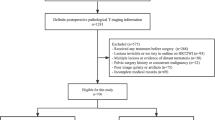

Daily-MRI data were collected from 19 patients with prostate cancer who received MRI based adaptive radiotherapy (ART) from May 2021 to July 2022. Daily MRI scanning was performed on Unity MR-linac (Elekta, Stockholm, Sweden) using T2 3D LSHQ and T2 3D HSLQ sequences within 30 min, respectively. Sixty pairs of 1.5 T MR images in total from nineteen patients who received ART were retrospectively analyzed in this study. The number of collected paired image sets (LSHQ and HSLQ images) varied from 2 to 5 pairs for each patient. Imaging data of LSHQ and HSLQ images were 20,400 slices, respectively, for model training. The acquisition time of HSLQ (T2 3D Tra 2 min) and LSHQ (T2 3D Tra) sequence were 117 s and 411 s respectively. The MRI imaging protocols of HSLQ and LSHQ were shown in Additional file 1: Appendix A.

Furthermore, Images of 139 patients with prostate cancer were collected to train a data augmentation model to increase the size and diversity of the training set. Twenty of them, who were not included in the training of main model (19 patients), had 3.0 T simulation MR, LSHQ MR, and HSLQ MR images (2D slices: n = 6800). Simulation-MRI scanning was performed using a 3.0 T MRI simulator (Discovery MR750w, GE Healthcare) with a T2-fs-propeller sequence. The Simulation-MRI imaging protocols were shown in Additional file 1: Appendix A.

Institutional Review Board approval was obtained for this retrospective analysis, and the requirement to obtain informed consent was waived. All the patient data were de-identified.